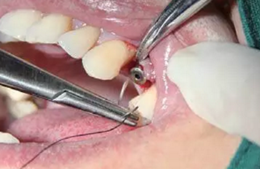

翻瓣與植入種植體

注意翻瓣不能太大,只需將窩洞頂端及周邊充分暴露即可。檢查種植窩洞頂端邊緣的骨壁情況,將窩洞頂端的高點(diǎn)去除,防止其干涉愈合基臺的就位。植入種植體植入時通過扭力扳手來確定最終的植入扭力,并判斷是否合適放置愈合基臺,也可以通過松動度測量儀測量ISQ值來判斷。

圖4 小翻瓣暴露窩洞頂端并去除高點(diǎn)